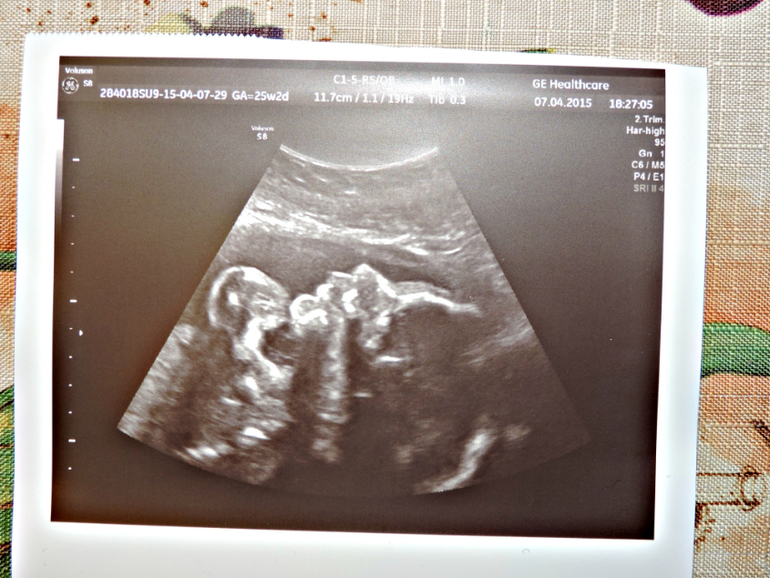

Сходила сегодня на УЗИ к Др.Озолине я просто в восторге , прекрасный врач , всё объяснила , всё показала , даже фотку дала и живот вытерла =))) и мы наконец то узнали , кто у нас будит МАЛЬЧУГАН =))) Вес его уже 780 гр , лежит головкой вниз , спинкой и попой с левой стороны живота и ножки наверху я прям пальчики видела на ножках , носик , губки и ещё у нас обвитие пуповины вокруг животика , но врач сказала , что обвитие лёгкое и ещё распутается , хотя меня мама родила с обвитием =) вообщем такой у нас был поход и теперь только к ней буду ходить =)